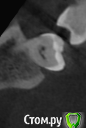

Александр1978 Опубликовано 2 марта, 2016 Автор Поделиться Опубликовано 2 марта, 2016 Сегодня КТ сделал,с прогой работать не могу,вот наделал срезы зуба,правильно/нет не знаю...что скажите,господа? Ссылка на комментарий

IvanK Опубликовано 3 марта, 2016 Поделиться Опубликовано 3 марта, 2016 Очень маленькие срезы.. скорее всего на "боковой" поверхности есть кариес Ссылка на комментарий